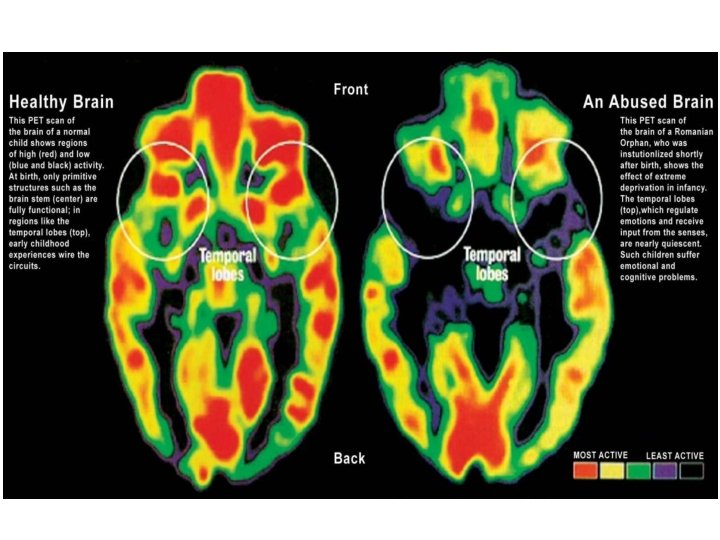

Gross anatomy